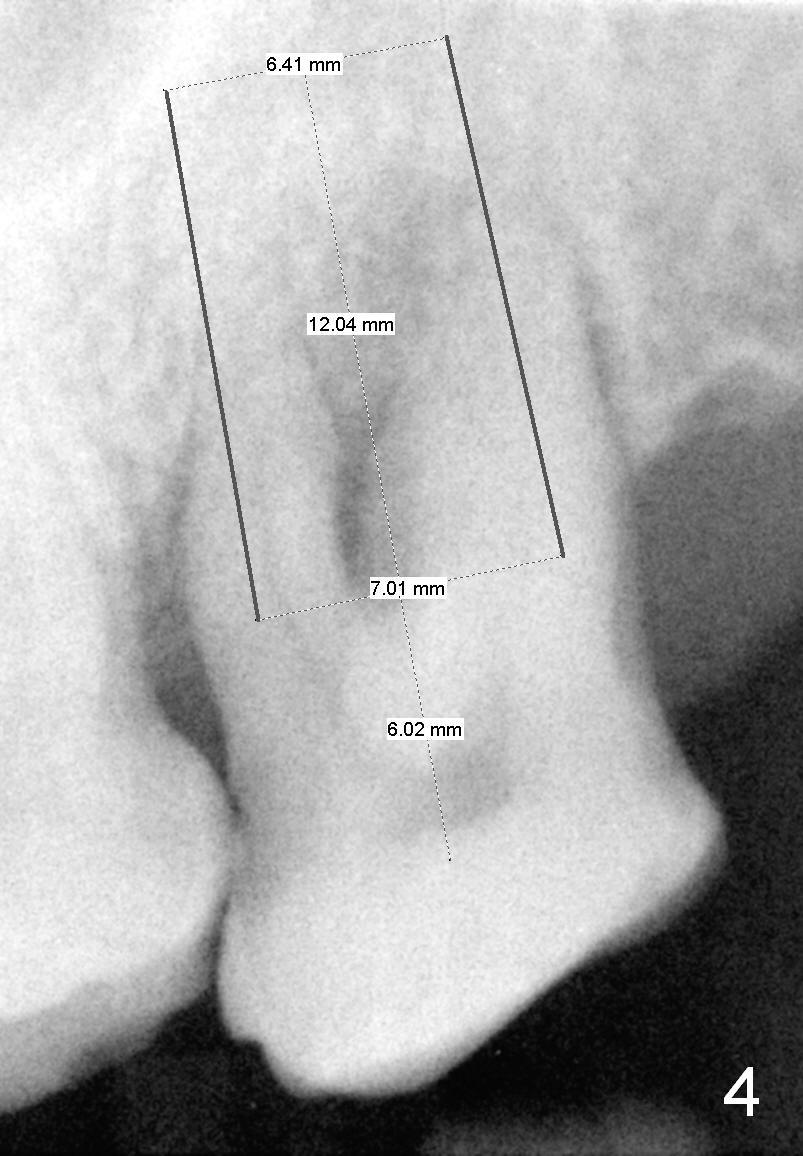

A 53-year-old man (ZB) has history of chronic periodontitis and bruxism. The tooth #18 has been extracted for a few years, while the tooth #15 is going to (Fig.1). Bone height for #15 immediate implant is not a problem (Fig.2-4; green line in Fig.2: sinus floor). After extraction (Fig.5 )socket to be treated with Clindamycin), use starter drill and a 2 mm pilot drill with stopper at 10 mm (Fig.6) on the crest of the septum (Fig.5 S). PA is taken with a parallel pin. Adjust the length accordingly. Subsequent osteotomy will be carried out with drills with stopper at 50 RPM. In brief, the implant does not need to be large. It should be placed as deep as possible (1-2 mm subcrestal mesially and/or distally), since the vertical height in the posterior region is limited. The margin of a cemented abutment is to be slightly subgingival. Use an immediate provisional to close socket gap, while to keep abutment margin from the gingiva. Use Collagen dressing before and after bone graft.